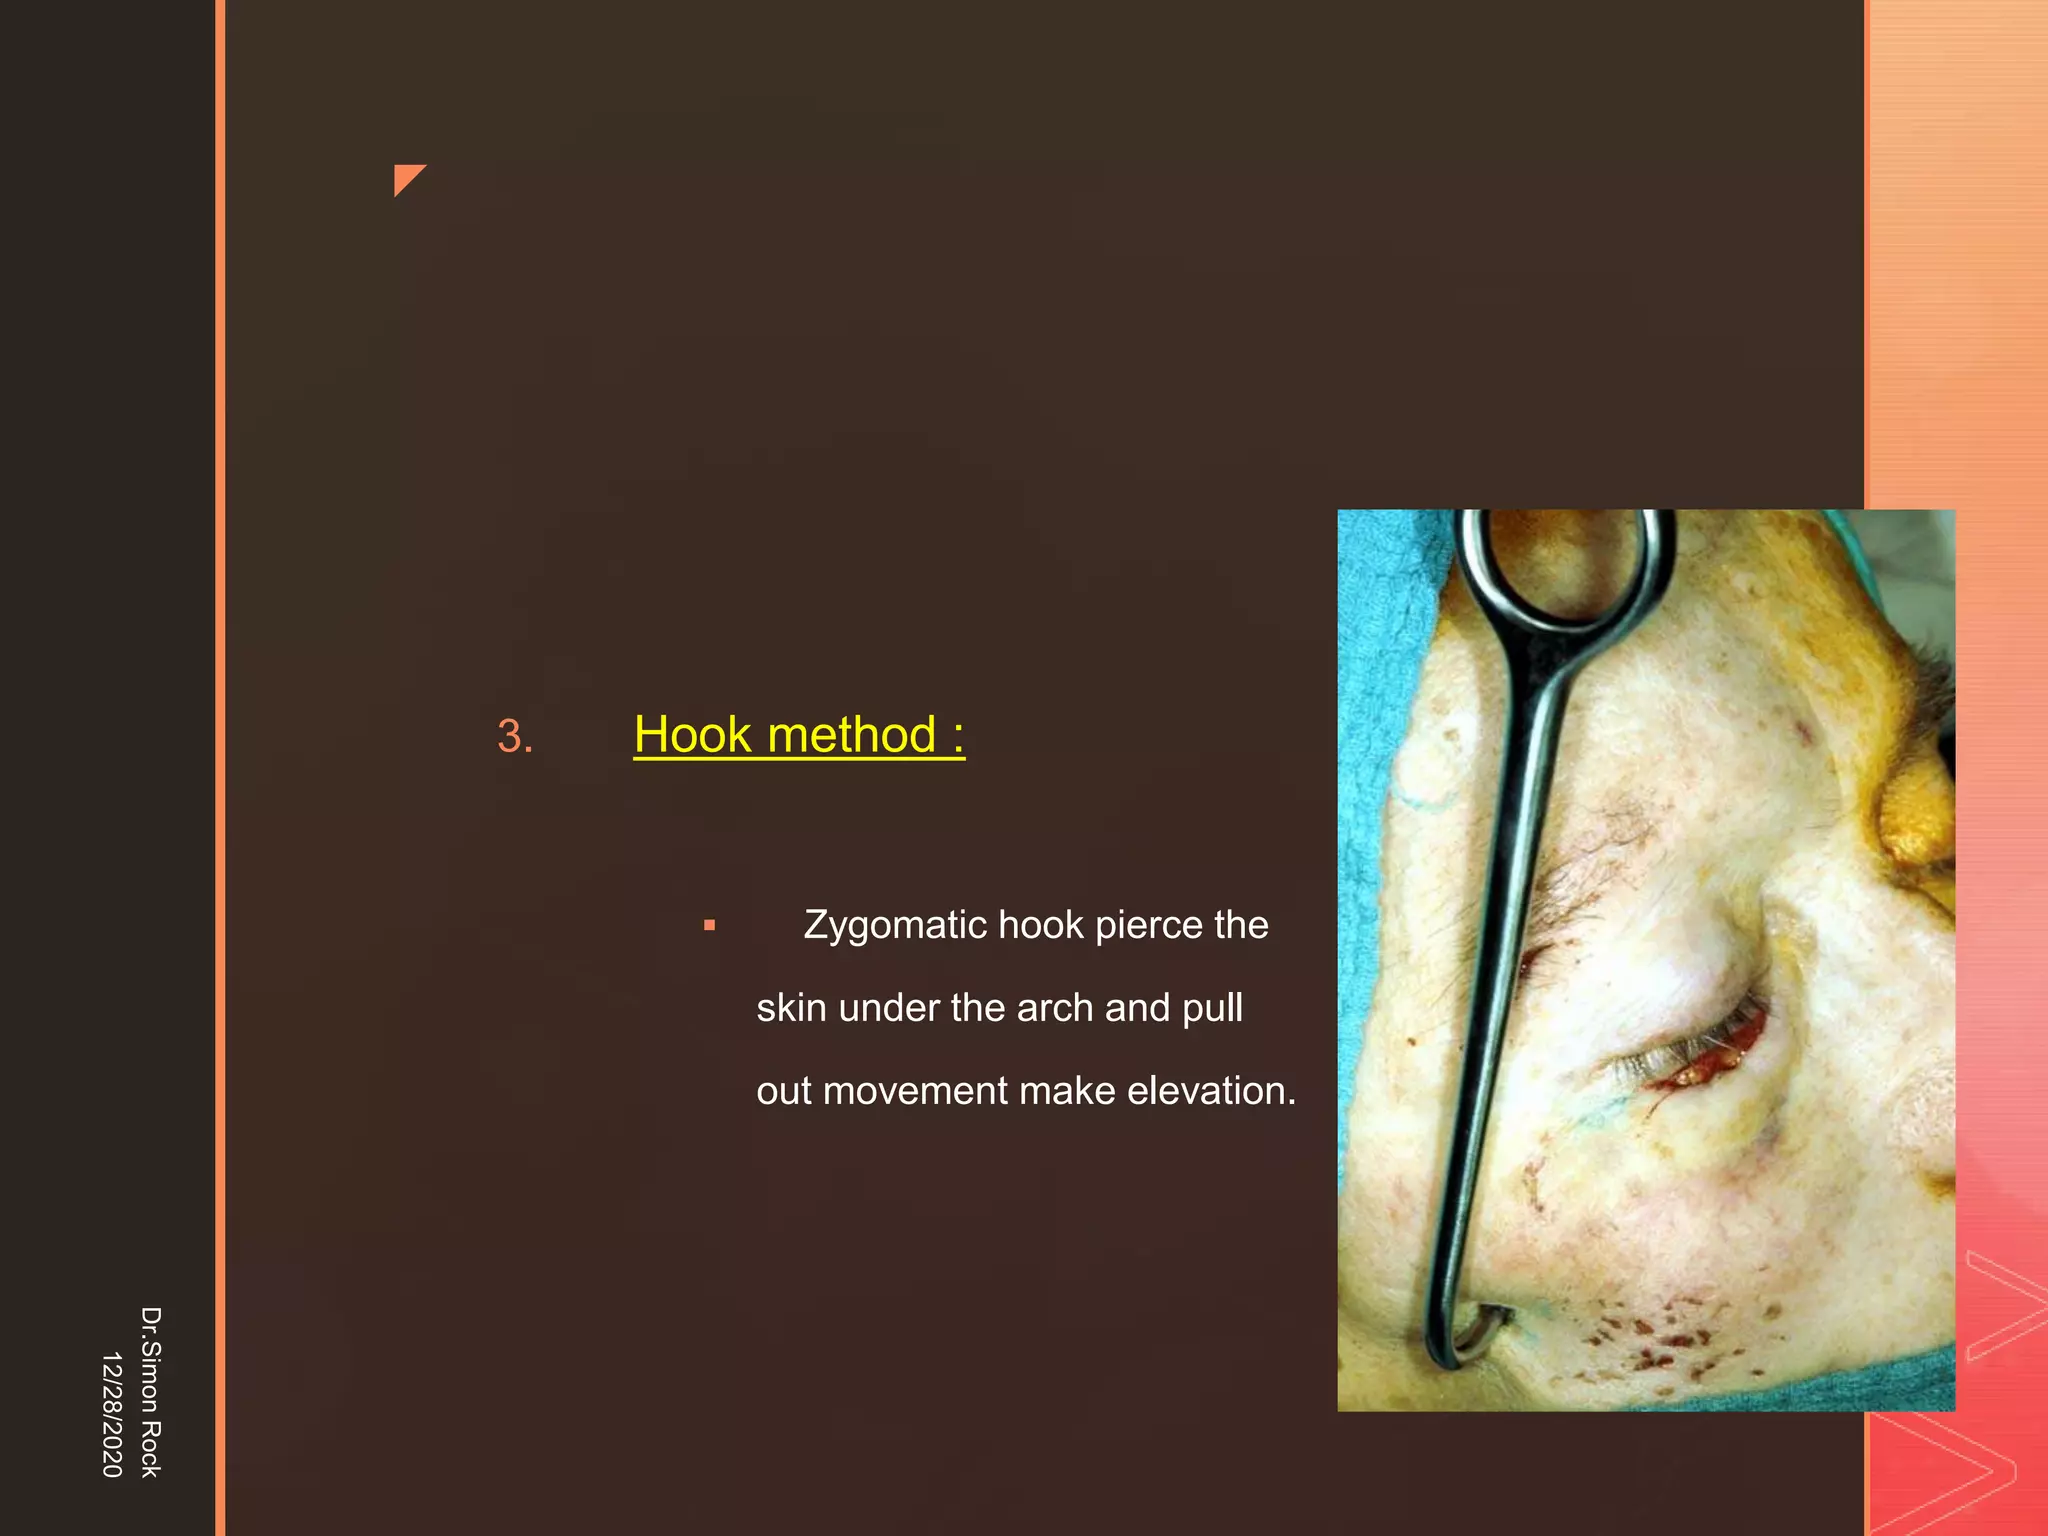

This document discusses the anatomy and fractures of the zygomatic bone. It notes that the zygoma forms the cheekbone and articulates with several other facial bones. Zygomatic fractures most commonly occur in the arch or body due to blunt trauma. Diagnosis involves checking for diplopia, ecchymosis, and other signs of orbital or facial bone involvement. Treatment may involve closed or open reduction based on the severity of displacement. Closed reduction techniques try to elevate the bone back into position without surgery, while open reduction requires surgical exposure and fixation of the fracture site.